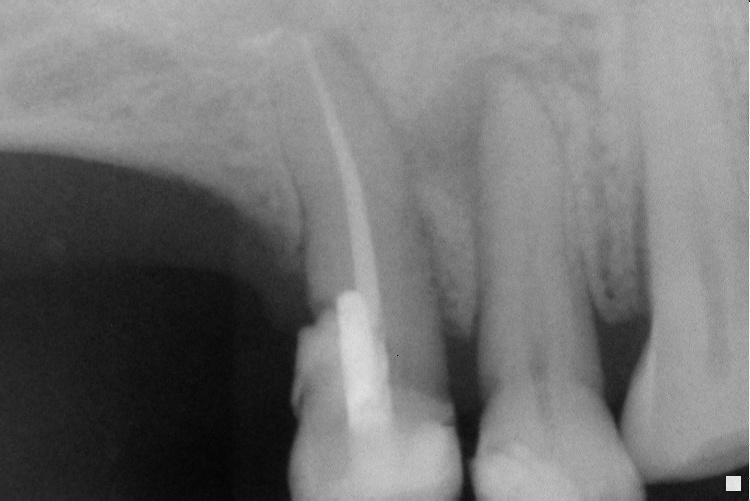

IO000001.jpg

2020-07-28 13:28 104K